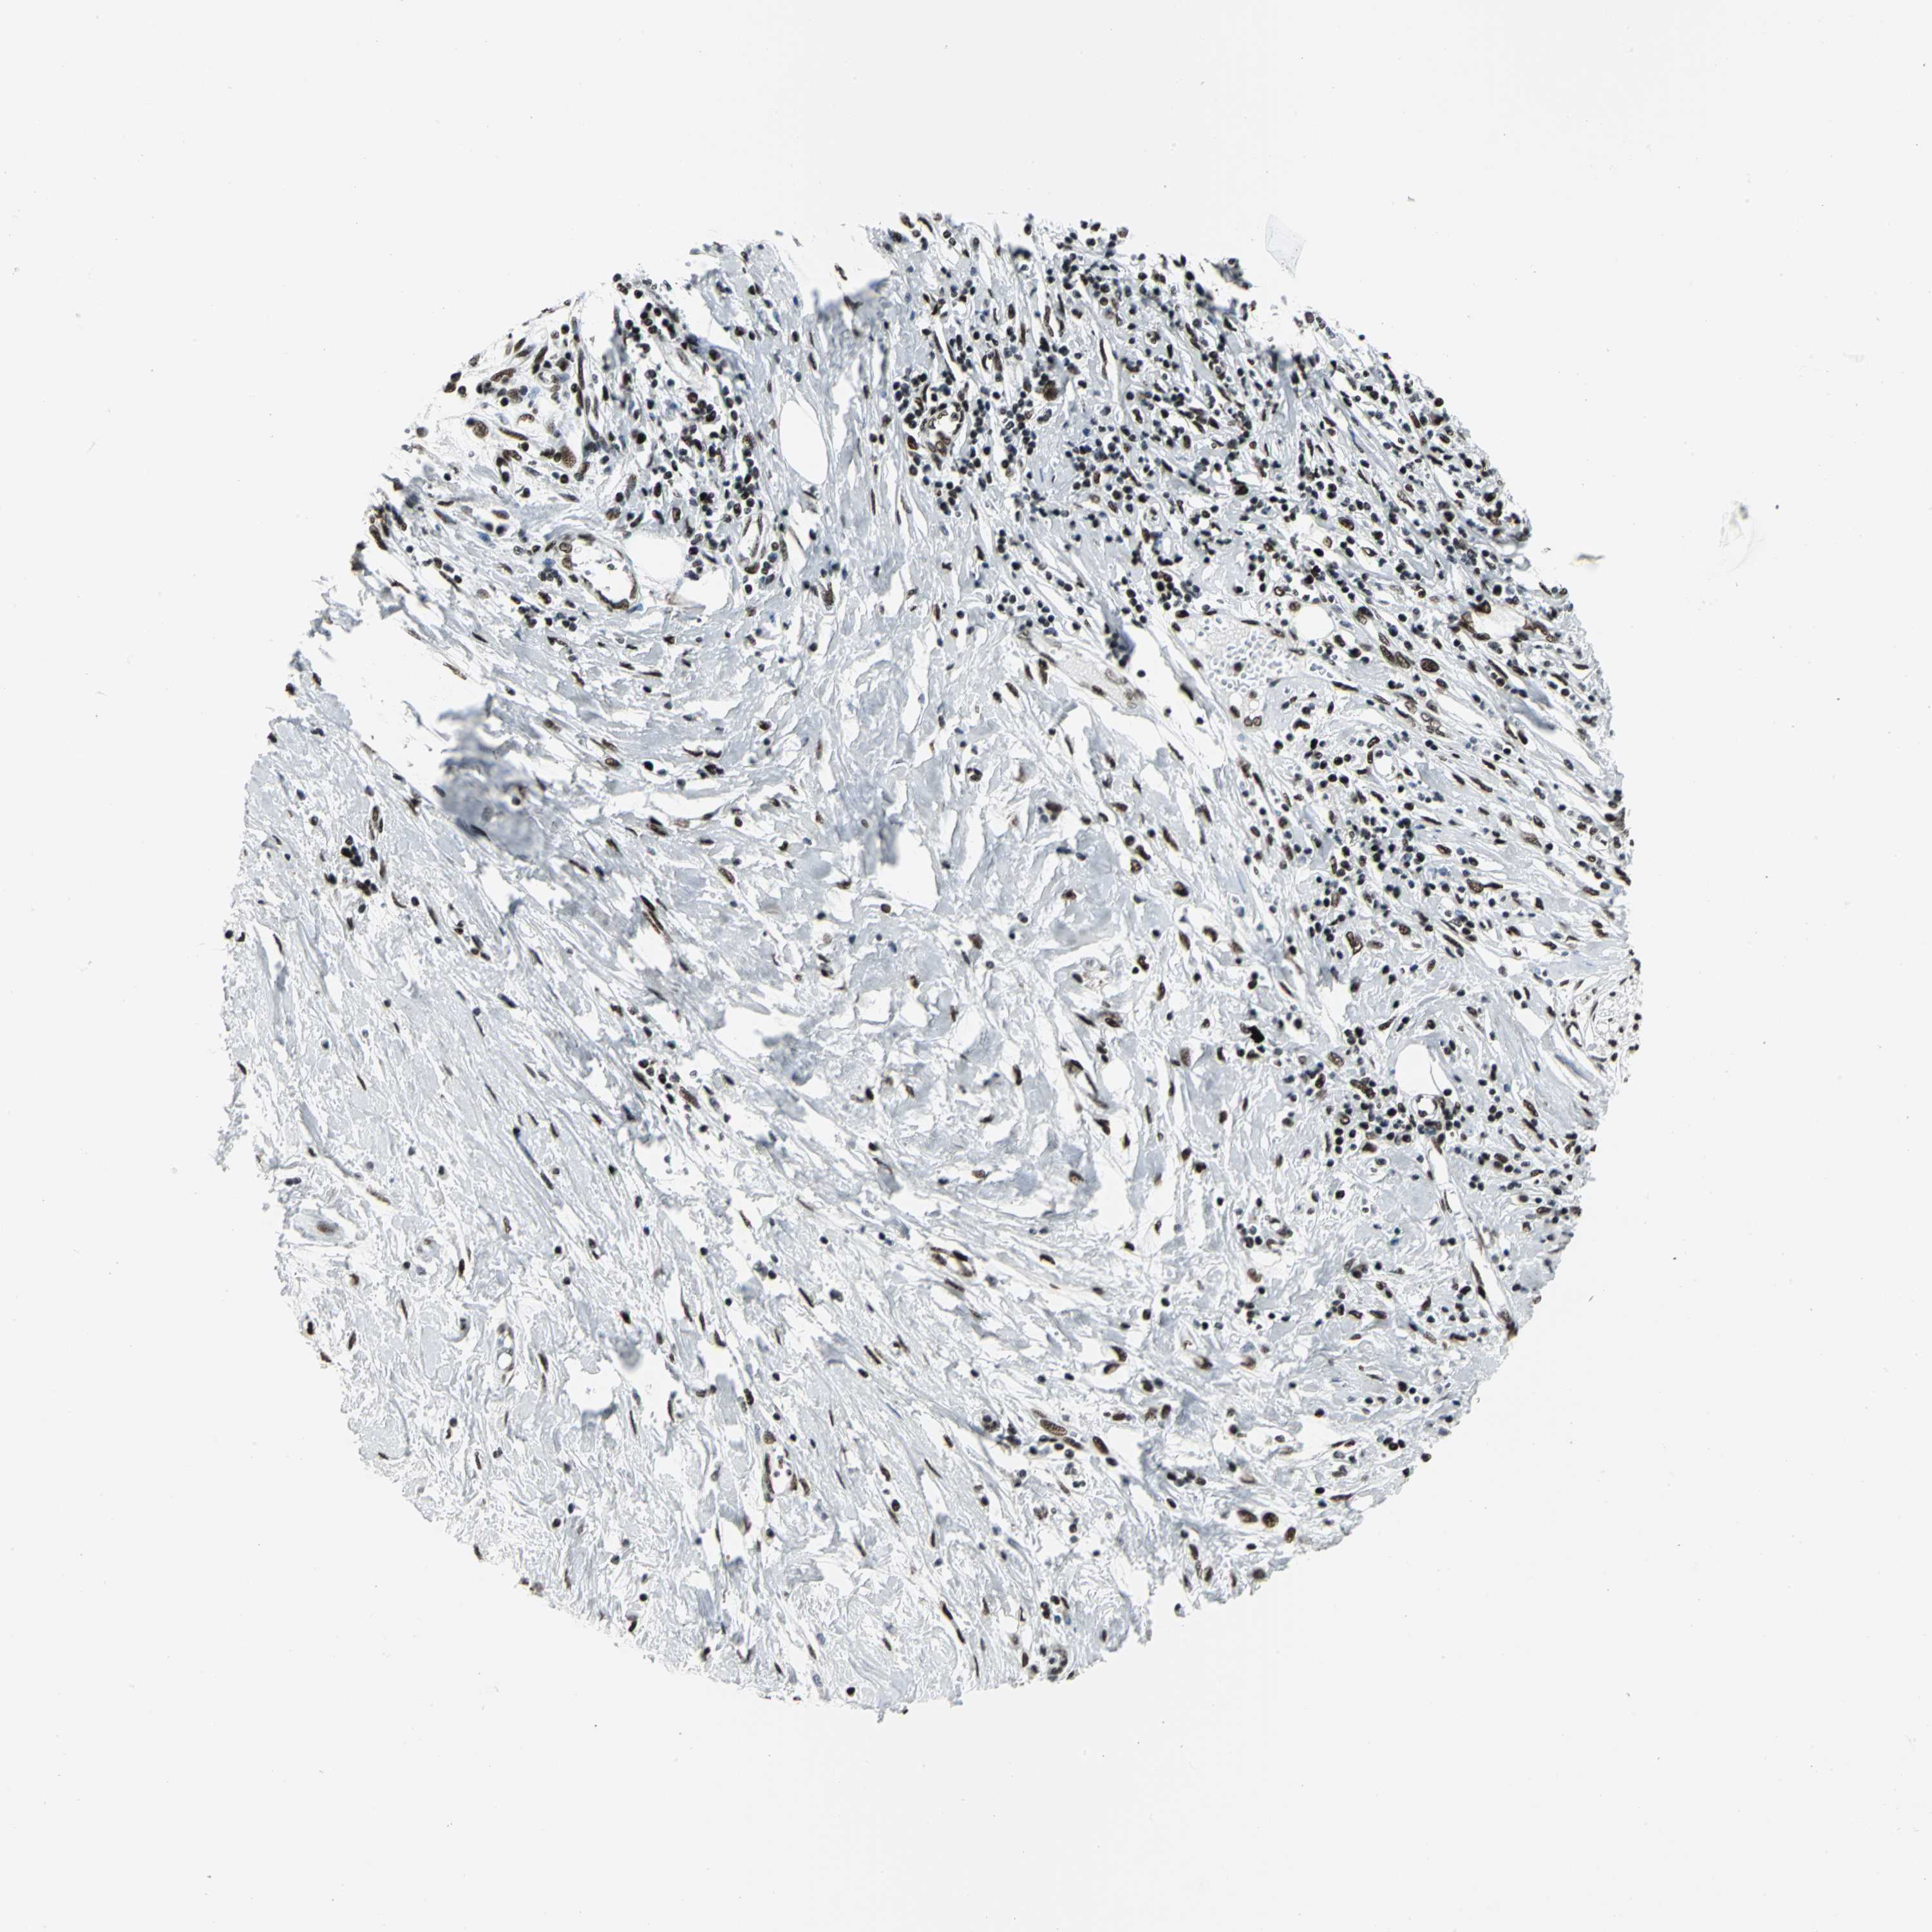

PANCREATIC CANCER - Protein expressioni

A mouse-over function shows sample information and annotation data. Click on an image to view it in a full screen mode. Samples can be filtered based on level of antibody staining by selecting one or several of the following categories: high, medium, low and not detected. The assay and annotation is described here.

Note that samples used for immunohistochemistry by the Human Protein Atlas do not correspond to samples in the TCGA dataset.

Antibody stainingi

Antibody staining in the annotated cell types in the current human tissue is reported as not detected, low, medium, or high, based on conventional immunohistochemistry profiling in selected tissues. This score is based on the combination of the staining intensity and fraction of stained cells.

Each image is clickable and will lead to virtual microscopy that enables deeper exploration of all samples and also displays staining intensity scores, fraction scores and subcellular localization as well as patient and tissue information for each sample.

Antibody CAB004208

Staining

High

Medium

Low

Not detected

Intensity

Strong

Moderate

Weak

Negative

Quantity

>75%

75%-25%

<25%

None

Location

Nuclear

Cytoplasmic/membranous

Cytoplasmic/membranous,nuclear

Adenocarcinoma, NOS

Adenocarcinoma, metastatic, NOS